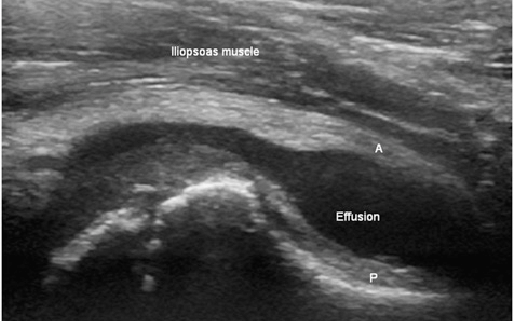

Diagnosis of transient synovitis involves a thorough physical examination followed by advanced imaging tests. Your doctor will often conduct blood tests to rule out other sources of hip pain like a bacterial infection. An ultrasound or an MRI can also be ordered to get a clear picture of the hip joint.